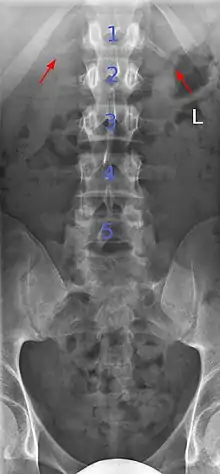

Lumbarization of sacral vertebra 1, seen as 6 vertebrae that do not connect to ribs.

Lumbarization is an anomaly in the spine. It is defined by the nonfusion of the first and second segments of the sacrum. The lumbar spine subsequently appears to have six vertebrae or segments, not five. This sixth lumbar vertebra is known as a transitional vertebra. Conversely the sacrum appears to have only four segments instead of its designated five segments. Lumbosacral transitional vertebrae consist of the process of the last lumbar vertebra fusing with the first sacral segment. [1] While only around 10 percent of adults have a spinal abnormality due to genetics, a sixth lumbar vertebra is one of the more common abnormalities. [2]

Sacralization of the L5 vertebra is seen at the lower right of the image.

Sacralization of the fifth lumbar vertebra (or sacralization) is a congenital anomaly, in which the transverse process of the last lumbar vertebra (L5) fuses to the sacrum on one side or both, or to ilium, or both. These anomalies are observed in about 3.5 percent of people, and it is usually bilateral but can be unilateral or incomplete (ipsilateral or contralateral rudimentary facets) as well. Although sacralization may be a cause of low back pain, it is asymptomatic in many cases (especially bilateral type). Low back pain in these cases most likely occurs due to biomechanics. In sacralization, the L5-S1 intervertebral disc may be thin and narrow. This abnormality is found by X-ray.